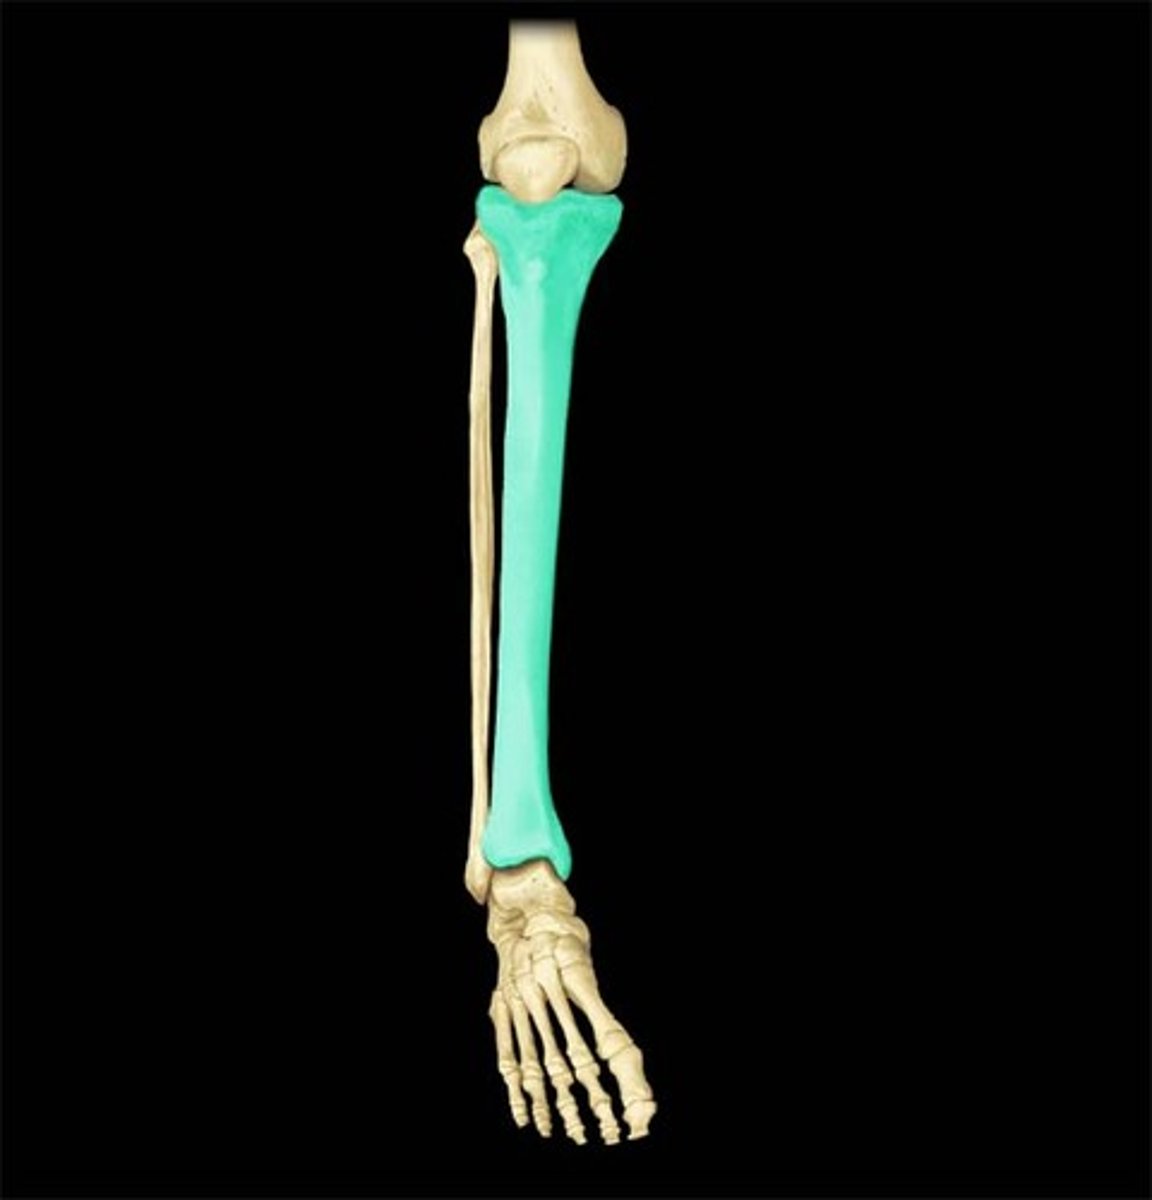

tibia

2

fibula

1